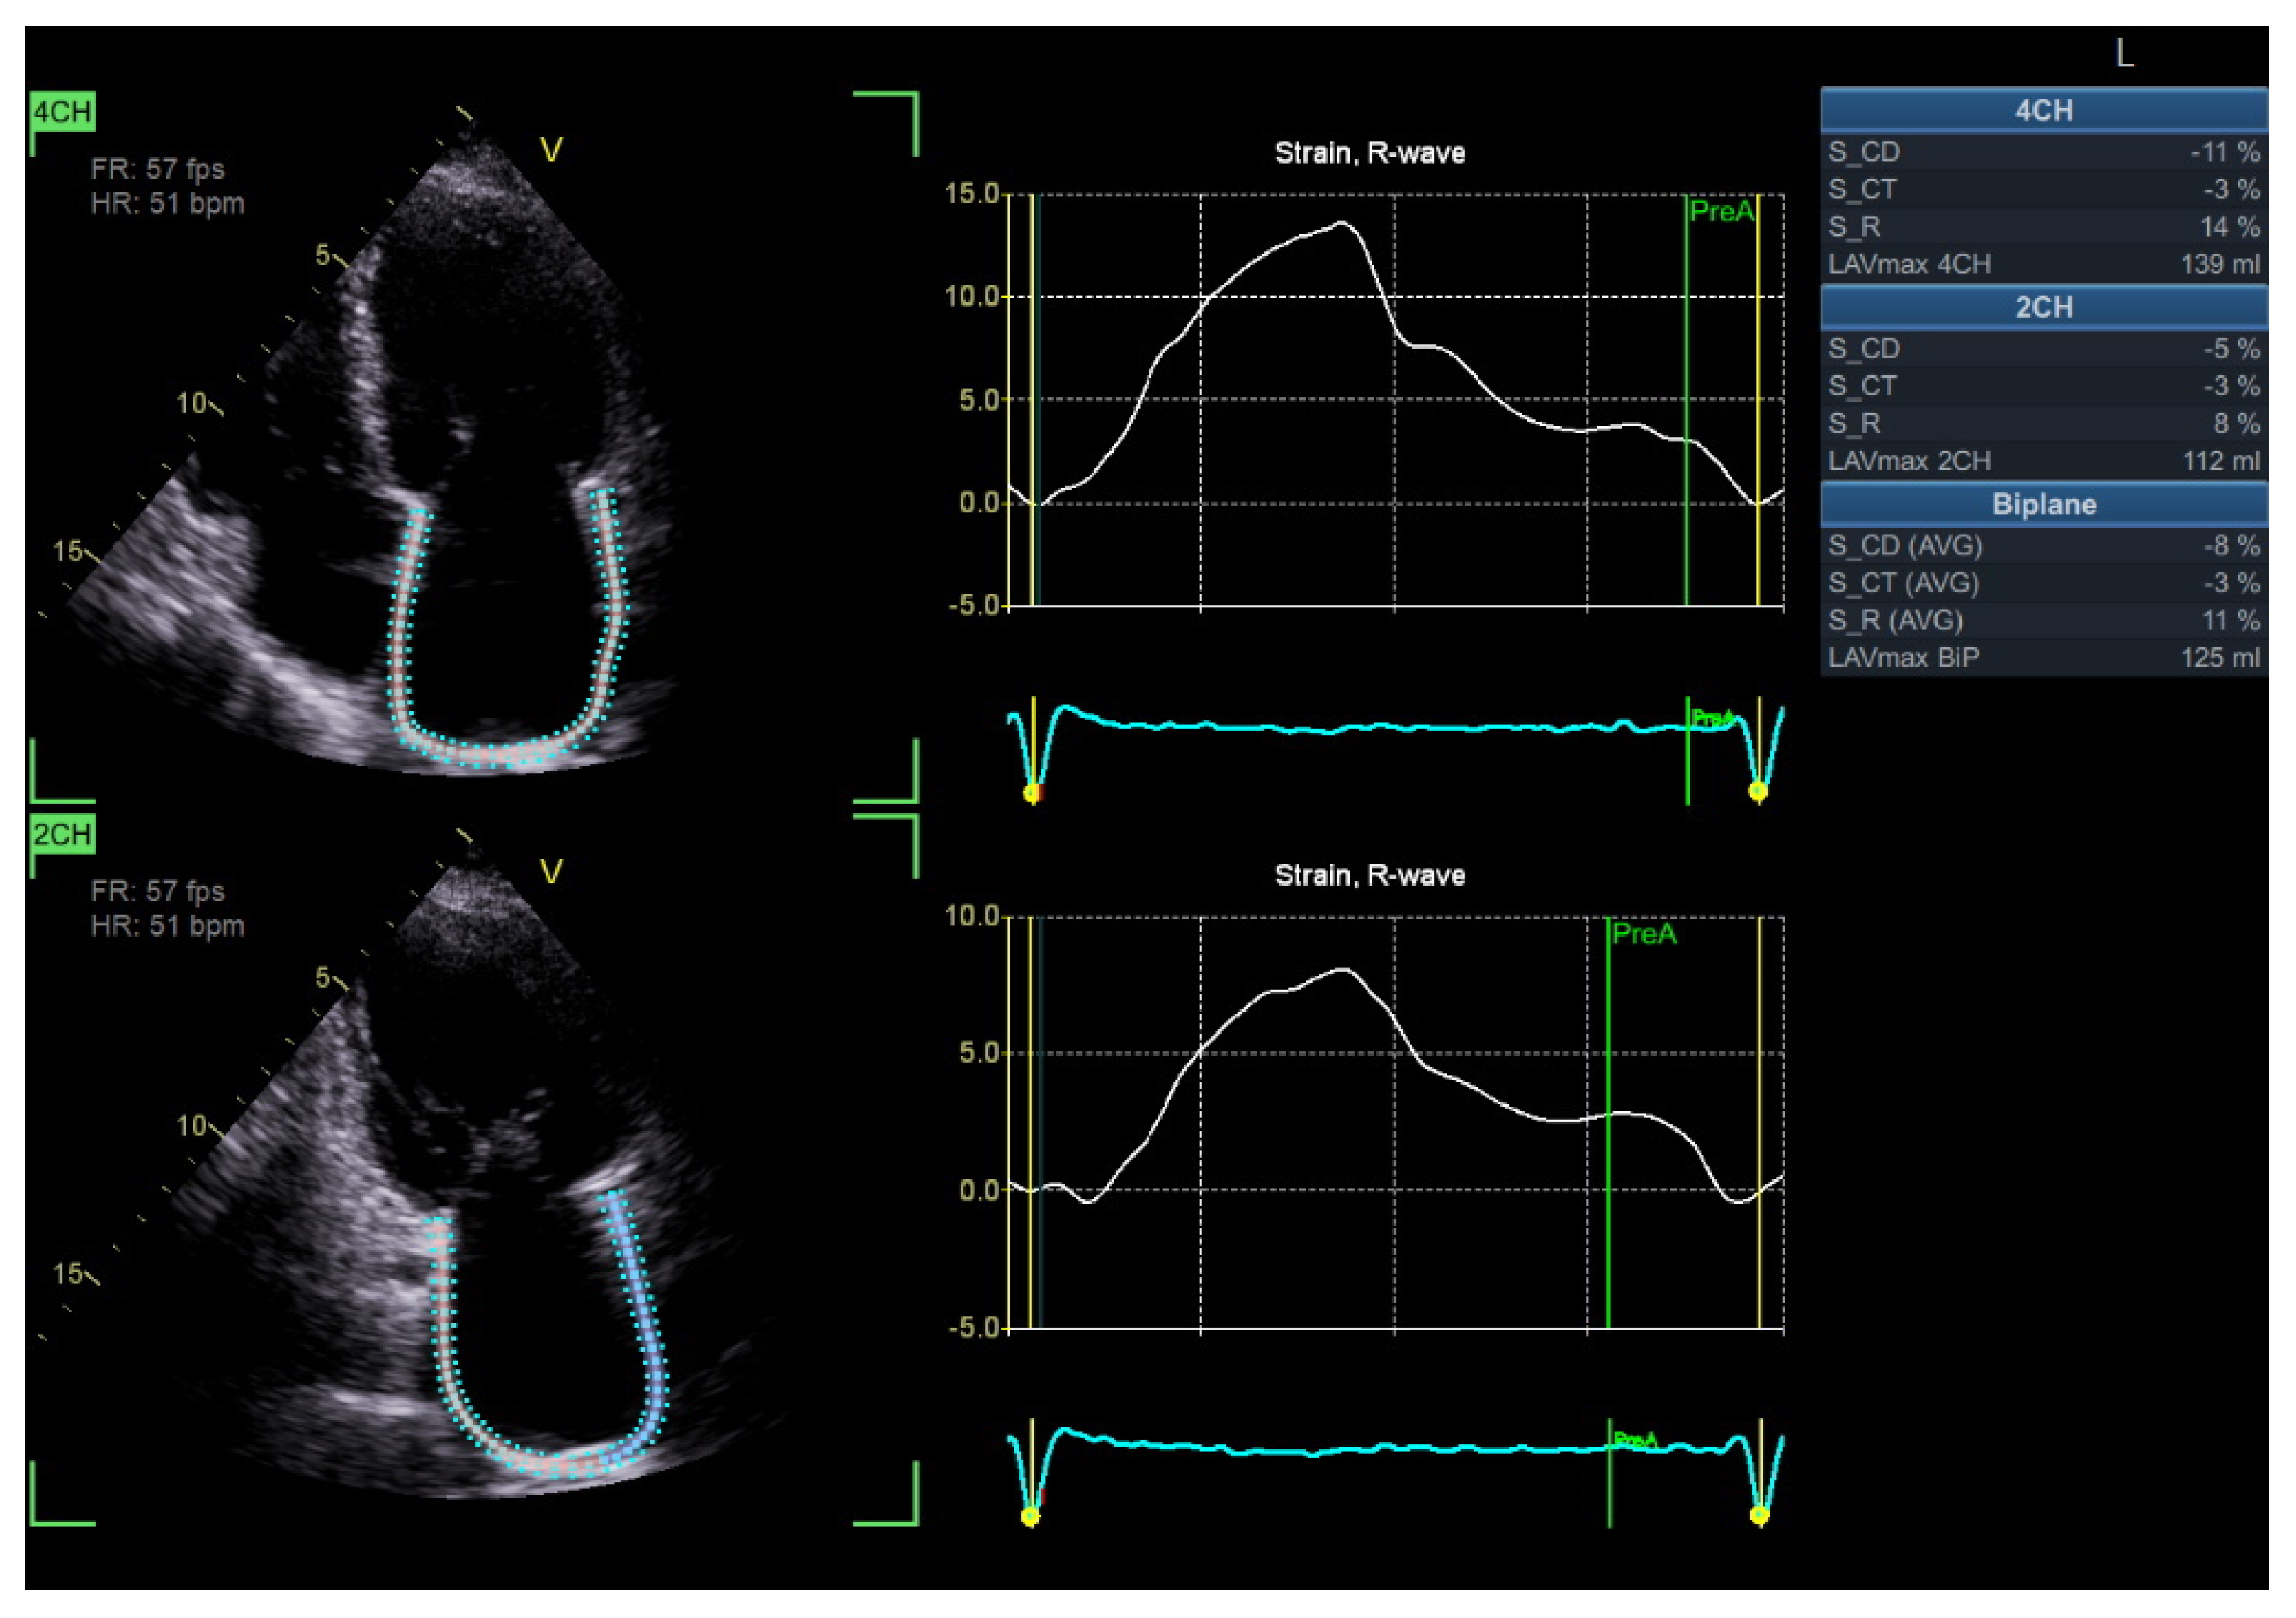

4.3. Speckle Tracking Echocardiography of the Left Atrium

| Speckle tracking LA | PALS, PACS (reservoir, conduit, contraction) | Requires good image quality; dependent on HR and rhythm; validation is required | -PALS and PACS are sensitive markers of subclinical diastolic dysfunction in the diabetic population -Predictor of elevated LVFP and HFpEF progression in the diabetic population -Associated with an increased risk of CV events |